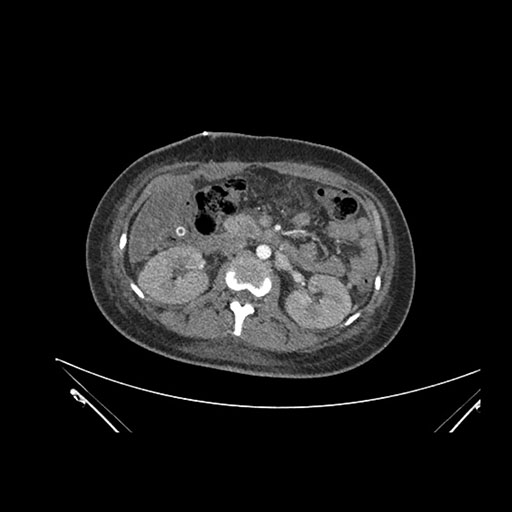

Imaging Analysis

Look through the patient's CT scan to identify any areas of concern for the necessary procedure.

Coronal Arterial

Coronal Venous

Based on initial findings, which issue(s) would you be most concerned about?